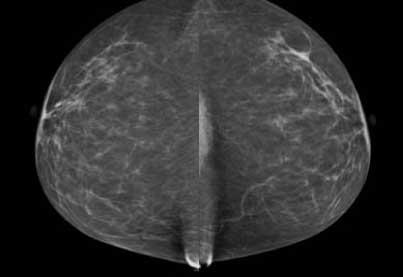

Recent studies have found that dense breast tissue is a strong independent risk factor for breast cancer. Breasts are composed of fat and fibroglandular tissue. Dense breast fibroglandular tissue appears white on a mammogram. Abnormalities and tumors also appear white on mammograms, causing them to be difficult to spot in dense breasts until the cancers are much larger and possibly in advanced stages.